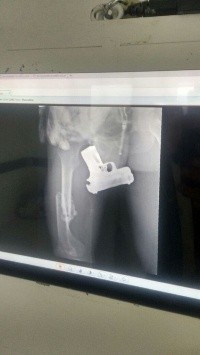

Sin embargo, tras llevarlo a las instalaciones de la Cruz Verde para realizarle el parte médico obligado, los doctores se percataron, gracias a una radiografía, que el hombre llevaba un arma de fuego real dentro del recto y entre los glúteos.

Fueron los médicos quienes se encargaron de retirarle el arma, para posteriormente ponerlo a disposición de las autoridades quienes se encargarán de determinar su situación legal, de acuerdo con las investigaciones correspondientes.